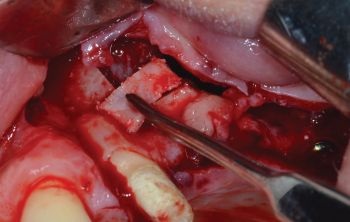

When Implants Go Rogue

Fig. 10: Bony window

Since the foreign body could further migrate inside the sinus because of physiological ciliary activity or cranial movements, it was crucial to use tools that assist the clinician: With the aid of a magnification system combined with coaxial illumination and a surgical suction unit with micro-cannulas, the implant was located in the position indicated by the preoperative CBCT.

Using microsurgical grasping forceps, the implant was securely clamped and then removed manually (Figs. 11–13).